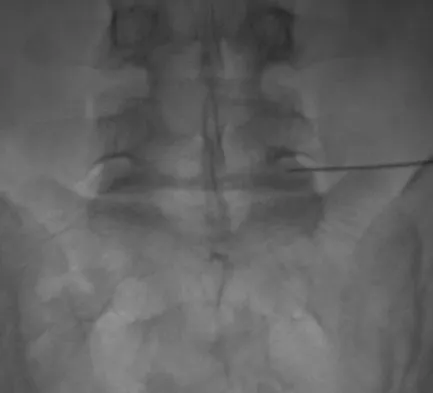

Figure 11 shows the radiograph of a 26-year-old man with type I diabetes mellitus who was struck by a motor vehicle. What is the most common complication associated with this pelvic fracture?

Explanation

The most common complication following acetabular or pelvic ring injury is deep venous thrombosis (DVT). Without prophylaxis, rates of DVT are as high as 70% to 80%. With prophylaxis, the rates are around 10%. Infection rates in surgical repair of acetabular fractures are relatively low but a history of diabetes mellitus and a significant Morel-Lavalle lesion certainly increase the risk. However, even with these two complicating factors, the rates of infection are still lower than 10%. Sciatic nerve palsy rates from the injury alone approach 20% and iatrogenic injury is usually less than 2%. Degenerative changes to the hip following this injury approach 20% to 25%, even with an anatomic reduction. Geerts WH, Code KI, Jay RM, et al: A prospective study of venous thromboembolism after major trauma. N Engl J Med 1994;331:1601-1606.